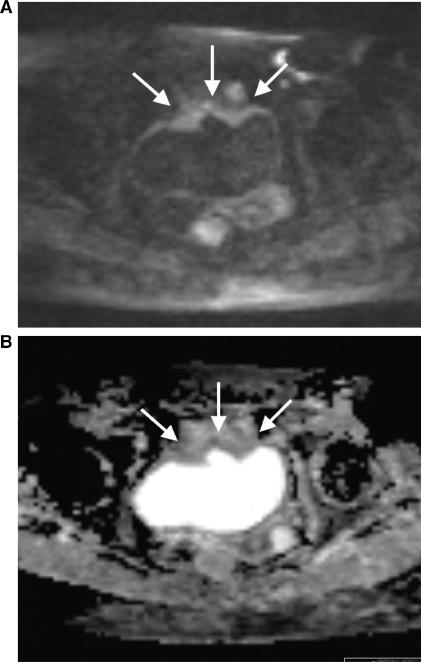

Diffusion-weighted magnetic resonance imaging (DW-MRI) appears to hold promise as a non-invasive imaging modality in the detection of early microstructural and functional changes of different organs. DW-MRI is an imaging technique with a high sensitivity for the detection of a large variety of diseases in the urogenital tract. In kidneys, DW-MRI has shown promise for the characterization of solid lesions. Also in focal T1 hyperintense lesions DW-MRI was able to differentiate hemorrhagic cysts from tumours according to the lower apparent diffusion coefficient (ADC) values reported for renal cell carcinomas. Promising results were also published for the detection of prostate cancer. DW-MRI applied in addition to conventional T2-weighted imaging has been found to improve tumour detection. On a 3 T magnetic resonance unit ADC values were reported to be lower for tumours compared with the normal-appearing peripheral zone. The combined approach of T2-weighted imaging and DW-MRI also showed promising results for the detection of recurrent tumour in patients after radiation therapy. DW-MRI may improve the performance of conventional T2-weighted and contrast-enhanced MRI in the preoperative work-up of bladder cancer, as it may help in distinguishing superficial from muscle invasive bladder cancer, which is critical for patient management. Another challenging application of DW-MRI in the urogenital tract is the detection of pelvic lymph node metastases. As the ADC is generally reduced in malignant tumours and increased under inflammatory conditions, reduced ADC values were expected in patients with lymph node metastases.

弥散加权磁共振成像(DW-MRI)似乎有望成为一种非侵入性的成像方式,用于检测不同器官的早期微观结构和功能变化。DW-MRI 是一种对泌尿生殖系统多种疾病具有高灵敏度的成像技术。在肾脏中,DW-MRI 已显示出对实体病变进行特征描述的潜力。在局灶性 T1 高信号病变中,DW-MRI 也能够根据报告的肾细胞癌较低的表观扩散系数(ADC)值,将出血性囊肿与肿瘤区分开来。在前列腺癌的检测中也取得了有前途的结果。DW-MRI 与常规 T2 加权成像联合应用已被发现可提高肿瘤检测的灵敏度。在 3T 磁共振仪上,与正常外观的外周带相比,肿瘤的 ADC 值较低。T2 加权成像和 DW-MRI 的联合应用也显示出在放射治疗后检测复发性肿瘤方面有很好的效果。DW-MRI 可能会改善常规 T2 加权和对比增强 MRI 在膀胱癌术前评估中的性能,因为它可能有助于区分表浅性和肌层浸润性膀胱癌,这对患者管理至关重要。DW-MRI 在泌尿生殖系统中的另一个具有挑战性的应用是检测盆腔淋巴结转移。由于 ADC 通常在恶性肿瘤中降低,而在炎症条件下升高,因此预计淋巴结转移患者的 ADC 值会降低。